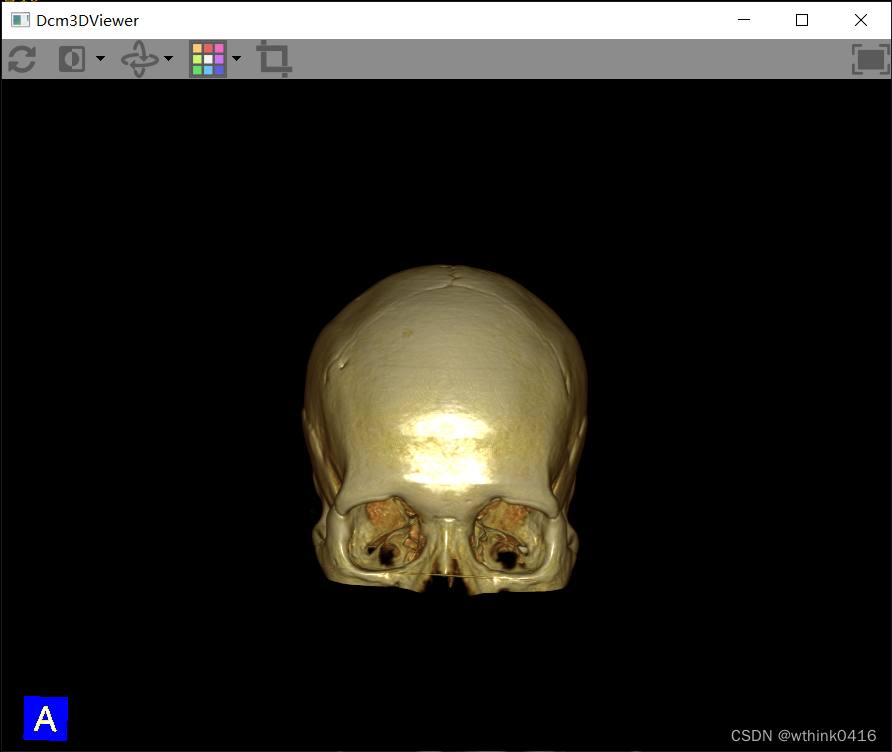

12、点击![]() 3D图标后,弹出三维重建窗口,该窗口为独立窗口,可以同时选择其他序列进行三维重建,方便进行对比

3D图标后,弹出三维重建窗口,该窗口为独立窗口,可以同时选择其他序列进行三维重建,方便进行对比